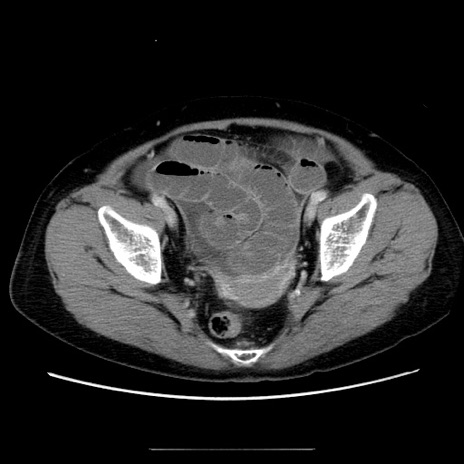

症例5(横断像)

【症例】70歳代女性

【主訴】お腹が張る

【現病歴】1週間くらい前から腹部膨満の自覚あり。昨日夜から増悪したため、本日救急外来受診。

【身体所見】意識清明、BT 36.5℃、BP 165/106mmHg、HR 80bpm、SpO2 98%、腹部:膨満、軟、自発痛・圧痛なし、触診にて不快感あり、腸蠕動音:減弱

【データ】WBC 12600、CRP 1.04